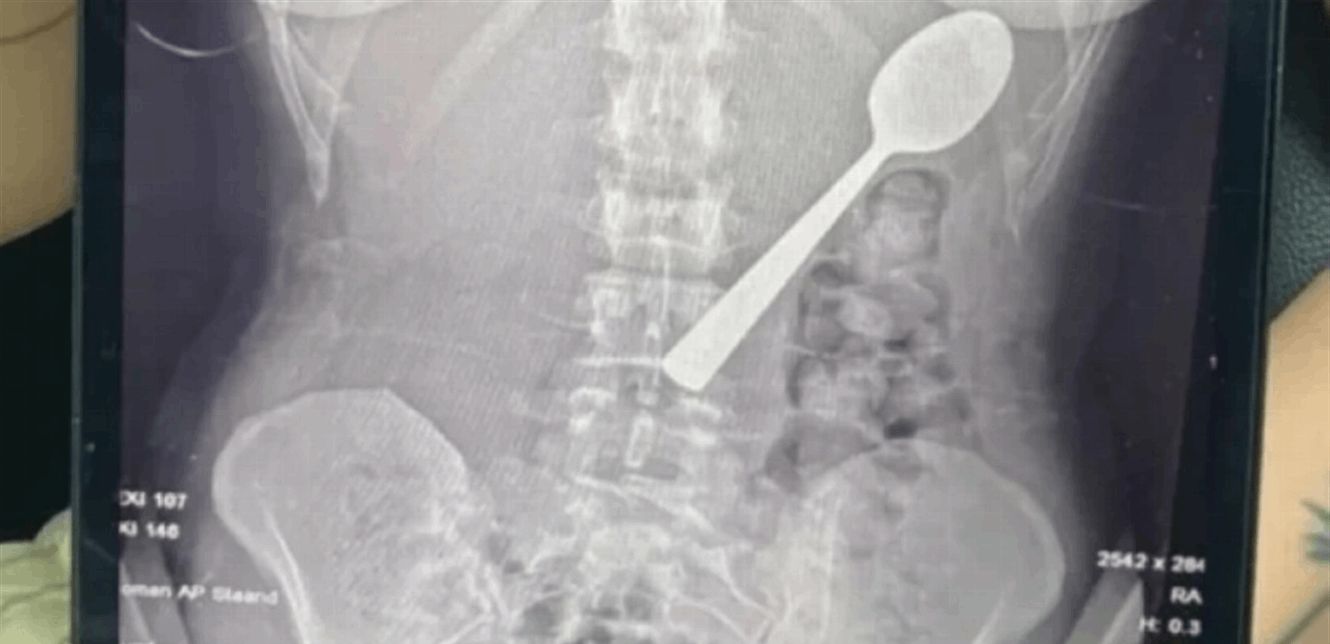

وعند مراجعة الأطباء، تبيّن أن الملعقة أكبر من أن تمر عبر الجهاز الهضمي بشكل طبيعي، ما استدعى تدخلاً عاجلاً. وبعد انتظار يومين تحت المراقبة، خضعت ريمي لعملية منظار معدة تحت التخدير الموضعي، حيث قام الأطباء بتدوير الملعقة بحذر داخل المعدة لسحبها، ما تسبب بنزيف طفيف والتهاب مؤقت في الحلق.